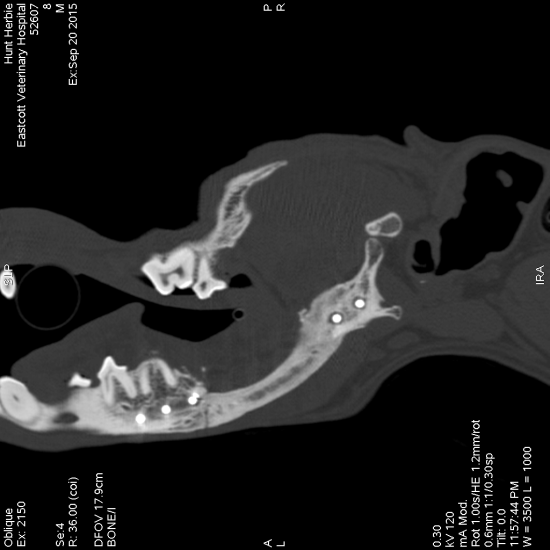

These were drawn onto a sagittal view of the affected mandible allowing detailed preoperative planning of the resection.

Right lateral view of a three-dimensional reconstruction of a CT scan of the skull of a dog showing measurements taken for surgical planning to ensure a 1 cm surgical margin for resection of an acanthomatous ameloblastoma.